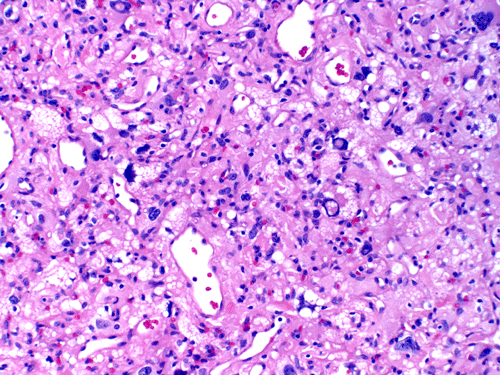

The mass consists of a mixture of spindle cells and clear cells. There is a rich vascular network (Panel A) with sinsusoidal dilatation but no anastomosis of the vascular channels. The endothelial cells appear lean and not protruding into the vascular channel. The clear cells appear to have foamy cytoplasm (̃ in Panel B). The nuclei are hyperchromatic and may appear slighly grooved or lobuated. On immunohistochemistry, the foamy cells are strongly reactive for inhibin (Panel C). These cells are also reactive for S100 protein (Panel D) and neural specific enolase (Panel E) . No immunoreactivity for epithelial membrane antigen (EMA) is observed (Panel F). The tumor is not immunoreactive for cytokeratin.

Microscopically, hemangioblastomas consist of foamy to clear stromal cells interspersed with endothelium lined vascular channels. Clear vacuoles within the stromal cells can be stained with Oil red-O or similar stain if applied to frozen sections. The stromal cells stain strongly for epidermal growth factor receptor (EGFR) and platelet-derived growth receptor factor alpha (PDGF-alpha) 12 and inhibin 13. The stromal cells are typically negative for epithelial membrane antigen (EMA) and cytokeratin 14. In a small number of cases, the stromal cells express glial fibrillary acidic protein (GFAP) 7, 14 and S100 protein 14. These staining results should be interpreted with case as they may represent entrapped glial cells. The admixed capillaries will stain for with typical endothelial markers (Factor-VIII and others) 15, but the stromal cells are typically negative for the endothelial markers. To this date, the pathogenesis and cell origin of hemangioblastomas is not certain.